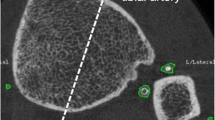

Abdominal Aortic Calcification

AAC was assessed from lateral spine DXA scans, obtained at the baseline for this study (2003) and 4–5 years prior (1998/99) using a Hologic 4500A scanner (Hologic, Marlborough, MA, USA). AAC was scored from 0 to 24 (AAC24) using established methods [16,17,18] by a single blinded experienced investigator (JTS). Presence of AAC was categorised as either having (AAC24 score ≥ 1) or not having (AAC24 score of 0) evidence of AAC at the baseline bone structure evaluation for this analysis. AAC was categorised using established [16, 19] groupings of the extent of AAC for CVD outcomes: low (AAC24 score 0 or 1), moderate (AAC24 score 2–5) and extensive (AAC24 score ≥ 6). Similarly, progression of AAC in the 4–5 years prior to baseline was categorised as either no progression (increase in AAC24 ≤ 1) or progression (increase in AAC24 > 1). AAC24 assessment is shown to be reproducible over a 4-year period [20], with very high intra-rater reliability reported from DXA-derived images (intraclass correlation coefficient: 0.91–0.95) [21]. Importantly, the same highly experienced trained imaging specialist (JTS) read both the baseline and the previous image together to determine the change, blinded to clinical data. Nevertheless, an increase in AAC24 score of one was considered as no progression to minimise the risk of misclassification due to possible image quality issues.